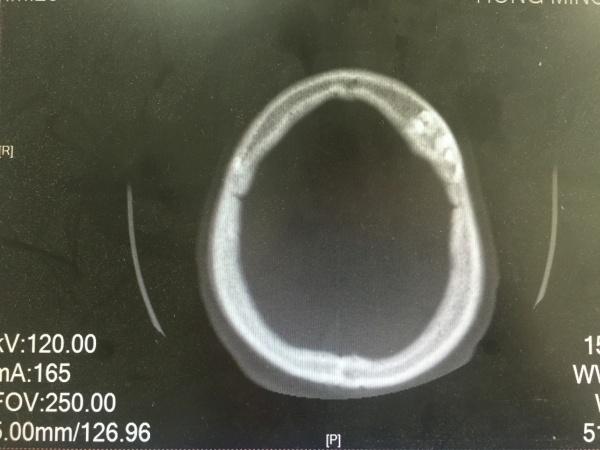

昨夜一位醉酒后外伤的病人,予以头颅CT检查发现的颅骨骨瘤,看着像在板障内,因患者醒酒后家属已送其回家,询问平素无明显不适,故无法跟踪及进一步明确。